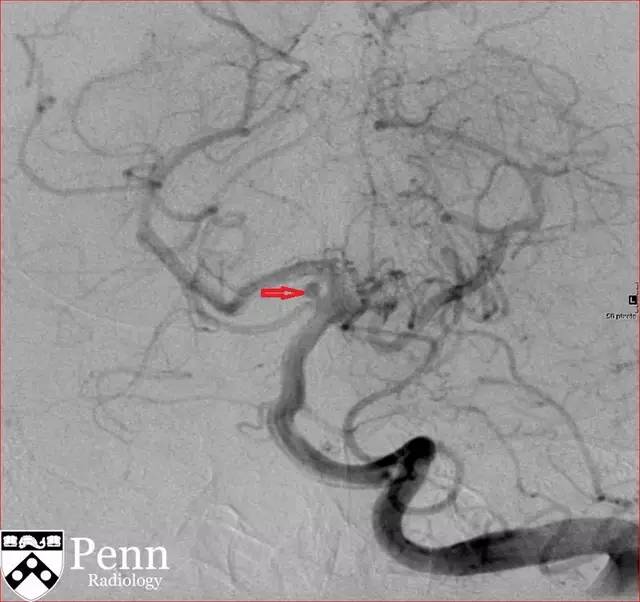

图 4 DSA 可见囊样动脉瘤(红色箭头)

CTA 示右侧右小脑上动脉一大小为 2.0 x 2.0 x 1.2 mm 的动脉瘤。

DSA:是诊断血管病变的金标准,具有非常高的空间分辨率和时间分辨率。可在动脉分叉处看到囊状影。破裂部位常可看到「墨菲乳头」。